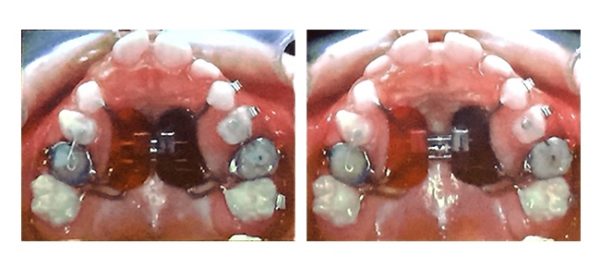

У вересні, в рамках академії безперервного навчання ортодонтів, Галина Матіюк прослухала курс

Dr.Marco Ross (Італія) “Early Orthodontic Treatment”. На знімках наведені випадки раннього лікування.